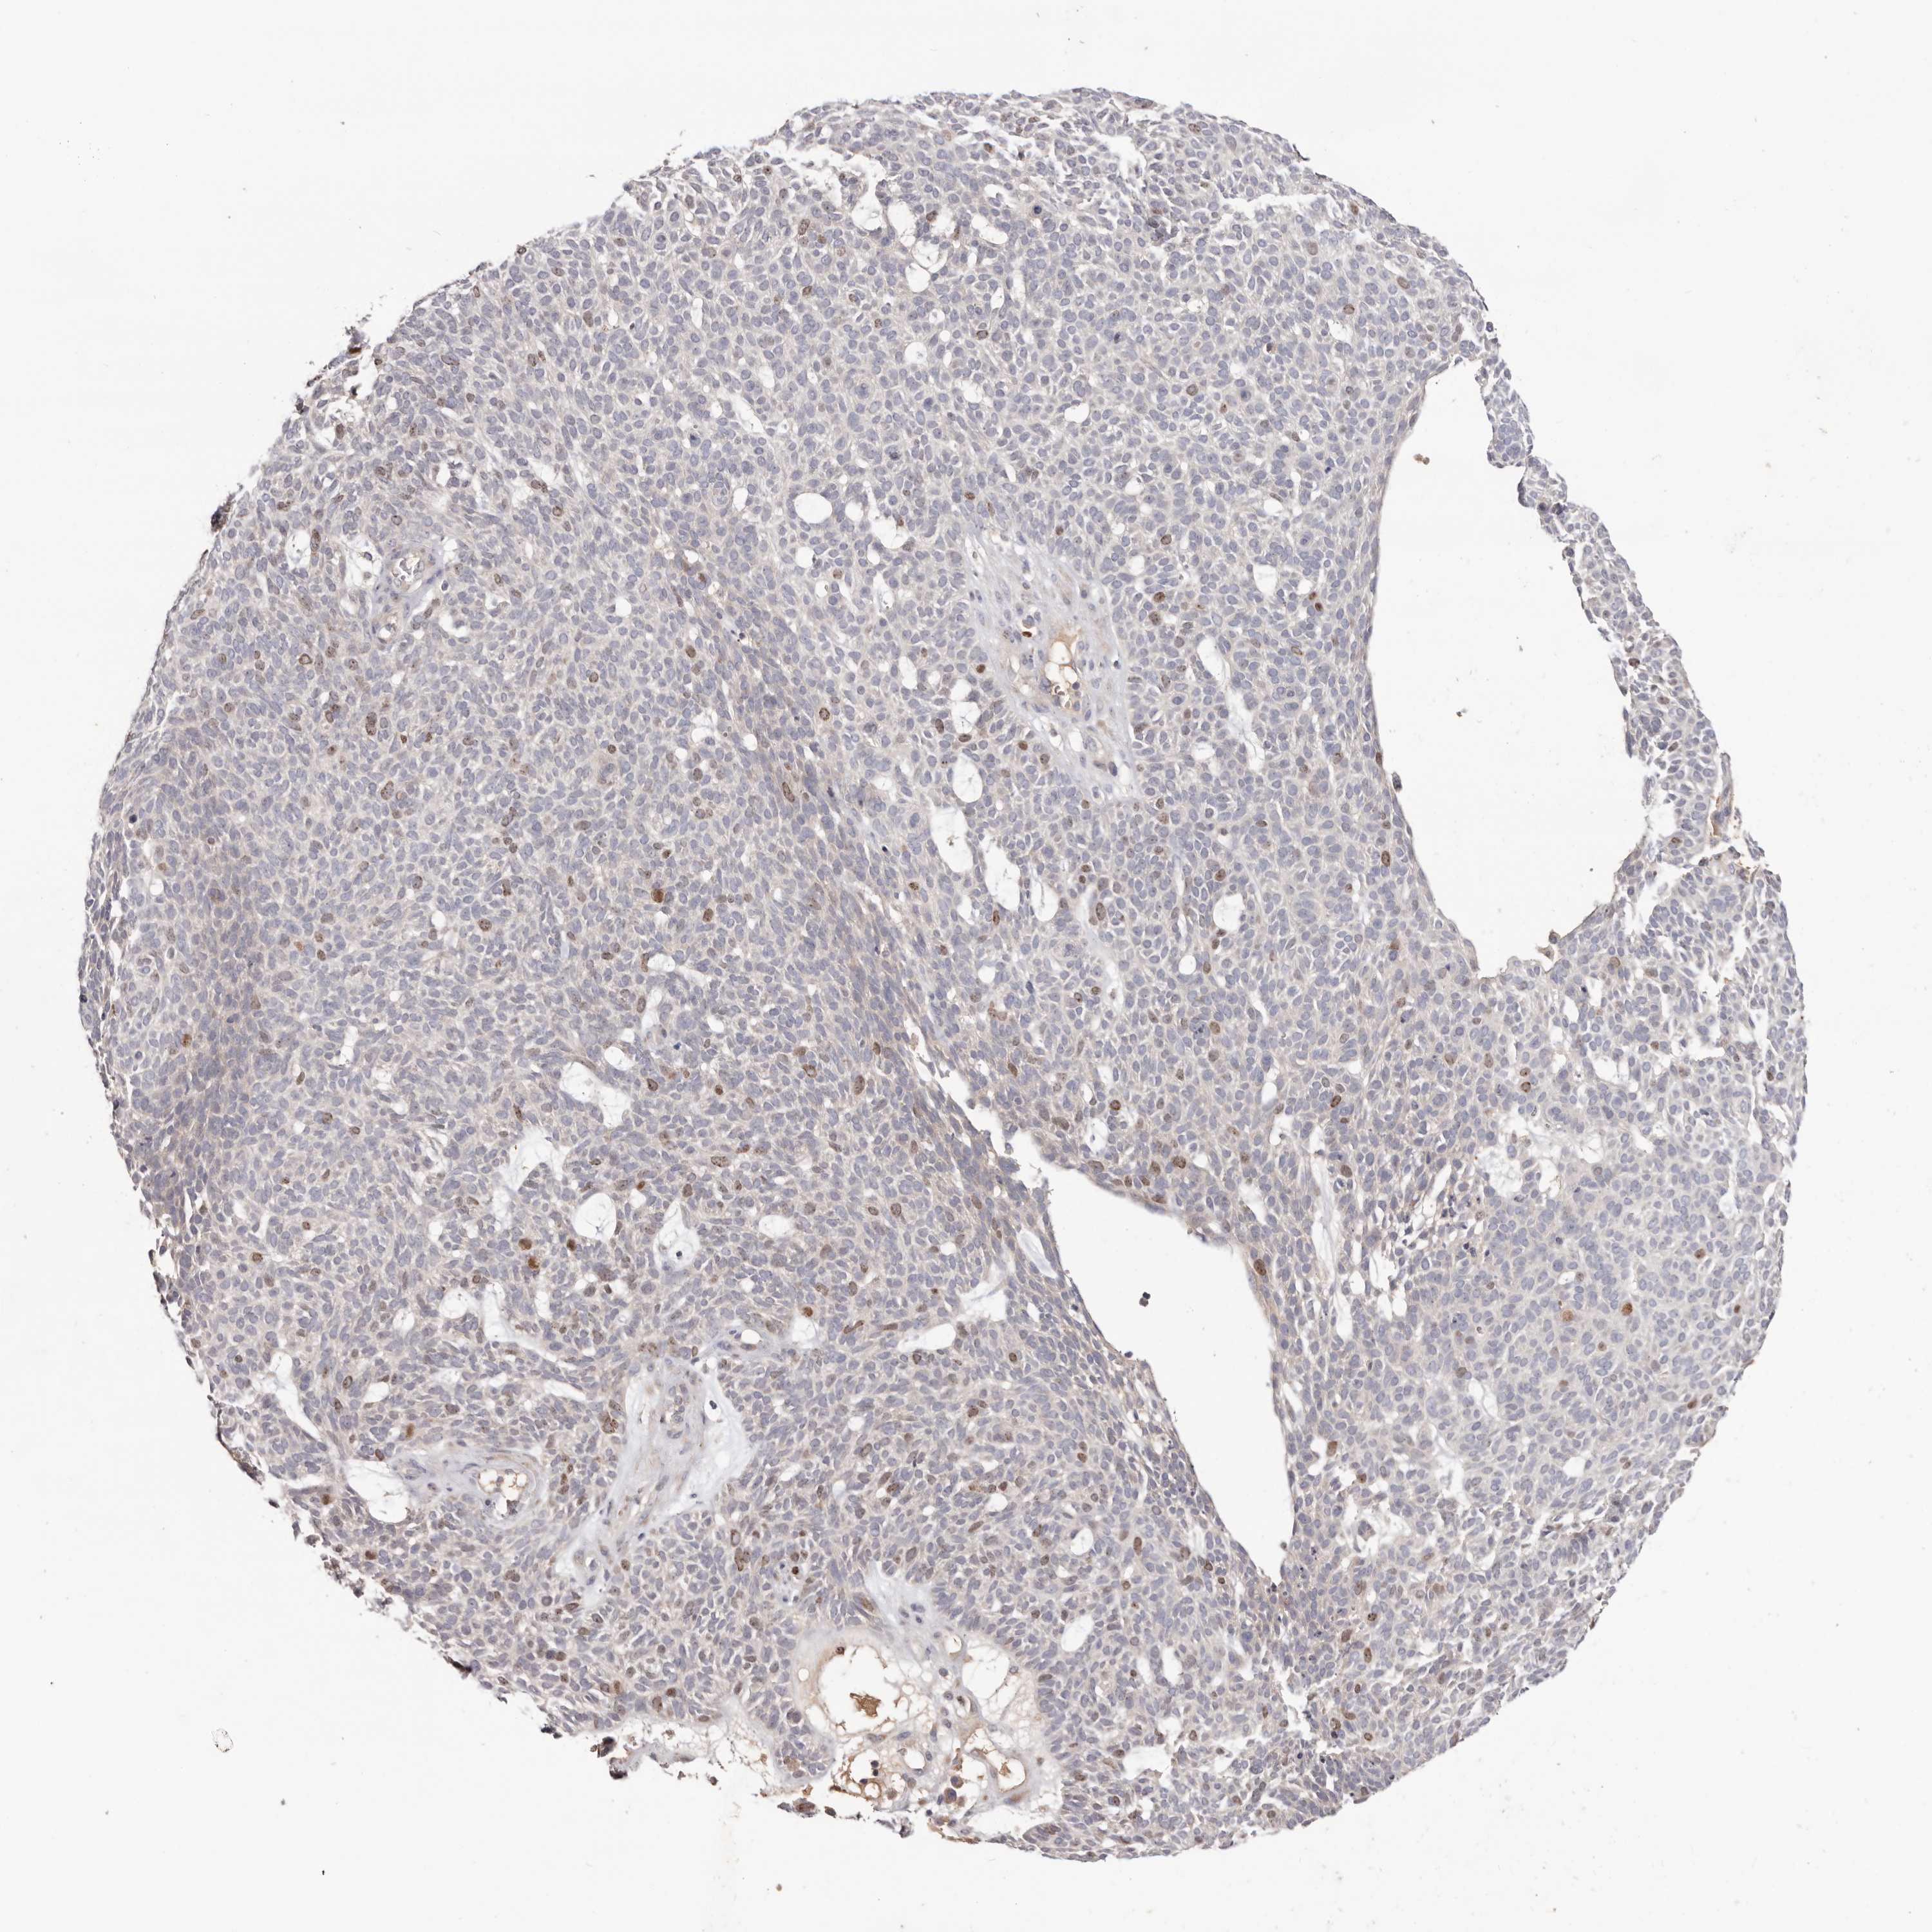

SKIN CANCER - Protein expressioni

A mouse-over function shows sample information and annotation data. Click on an image to view it in a full screen mode. Samples can be filtered based on level of antibody staining by selecting one or several of the following categories: high, medium, low and not detected. The assay and annotation is described here.

Each image is clickable and will lead to virtual microscopy that enables deeper exploration of all samples and also displays staining intensity scores, fraction scores and subcellular localization as well as patient and tissue information for each sample.

Antibody HPA028592

Squamous cell carcinoma, NOS